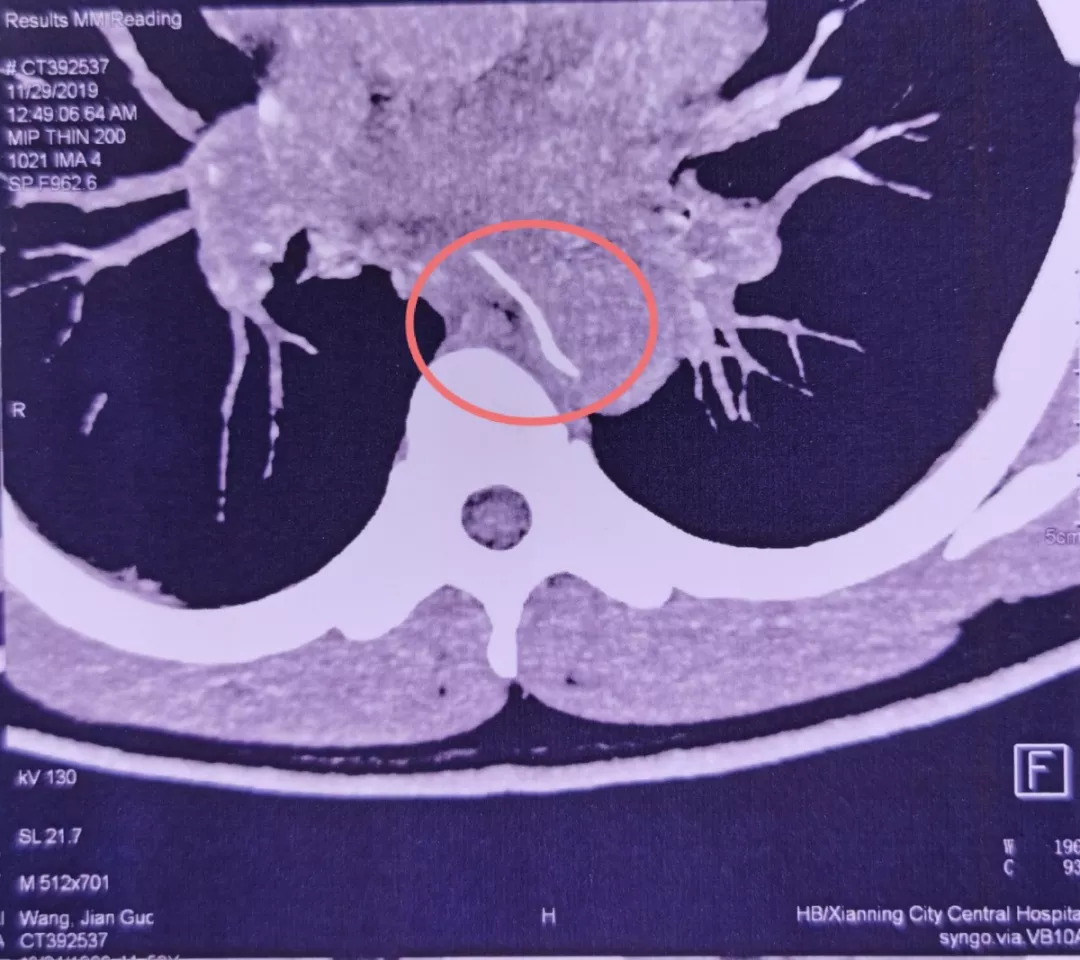

曹先生紧忙赶到当地医院。CT检查发现,一根鱼刺状异物横卧在食管,已经刺穿食管壁,尖头紧贴心脏主动脉!

救治团队当机立断,将其送入手术室,行全麻下急诊开胸探查。胸外科耿庆教授和汪巍副教授联手,从左侧开胸探查胸腔,小心翼翼松解胸腔粘连,清理干净分泌物后,发现鱼刺已刺穿食管。鱼刺尖端正处于主动脉弓下方,距离主动脉弓仅有1毫米,差点就要伤及主动脉。

检查发现,鱼刺像一把圆月弯刀,横插在食管和胸主动脉附近,已刺穿食管壁。如果盲目拔出,必定会形成主动脉破口。胸主动脉是人体最粗大的动脉血管,压力很高。一旦形成破口,出血犹如“大坝决堤”一般,难有抢救机会。

手术方案立即调整。胸外科黄杰教授团队接力上台。果然,鱼刺穿出食管,几乎整个扎进主动脉内,仅在外露出3毫米的刺尖。